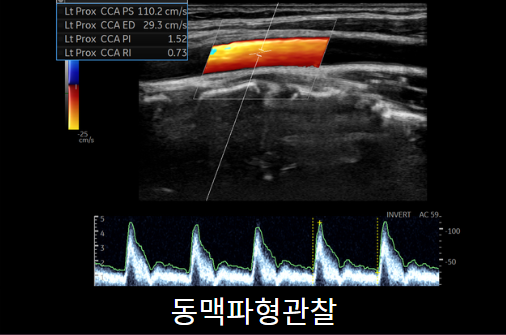

경동맥초음파

경동맥은 심장에서 뇌로 가는 혈관입니다. 고지혈증이 있는 경우 가장 많이 시행하며 혈관의 벽이 두꺼워져 경동맥이 좁아지지 않았는지, 혈전이 있는지 혈관의 파형을 확인 할 수 있습니다. 약 10분 정도 소요되며 금식은 필요하지 않습니다.